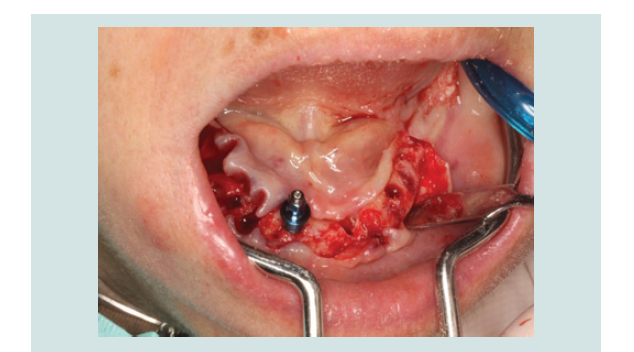

In March of 2013, a second surgery was performed in order to

place six implants in the maxilla. Th e same pre-operative and surgical

protocol was followed, and in this case a vertical incision was made

in the midline to facilitate the refl ection of the full-thickness fl ap. Six

implants were placed (2 SIN 4.0 x 10 mm implants and 4 EBi 4 x 4.1 x

8.5 mm implants) and submerged with cover screws. Primary closure

of the fl ap was achieved with 4/0 silk sutures (Inibsa, Portugal). Th e

patient continued to use the maxillary removable complete denture aft er relining it. Th e same post-operative protocol and instructions

were given to her, and in the follow-up visit the healing was again

favorable (Figure 1-9).